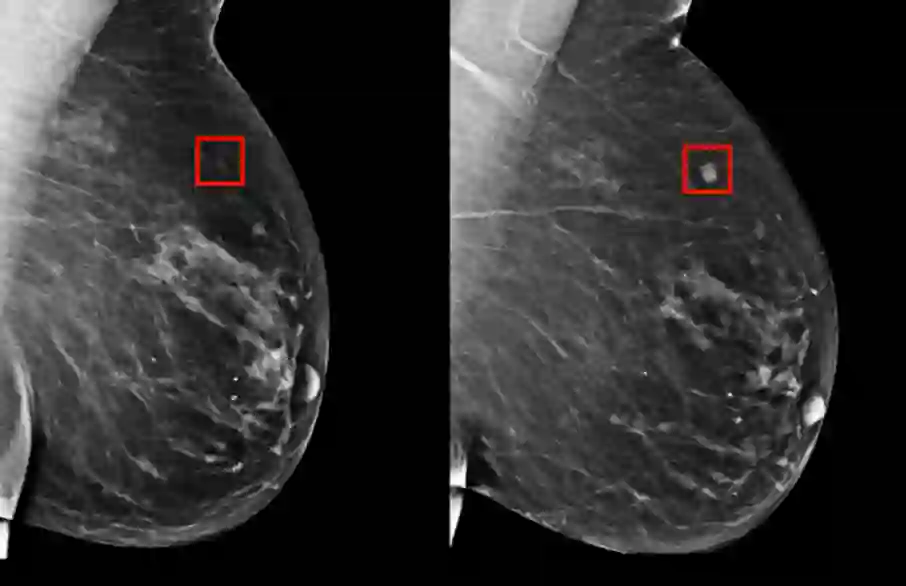

早发现、早诊断,是提高乳腺癌疗效的关键所在。当下对乳腺癌的检测包括乳腺 X 线摄影、超声(US),必要时则进行乳腺磁共振检查(MRI)。

乳腺 X 线摄影

乳腺 X 线摄影是近年来国际上推荐的乳腺癌筛查中的主要方法,这种方法较适用于乳腺密度相对较低的女性,而乳腺超声则相对比较适合于致密性乳腺。

亚洲女性的乳腺密度相对致密,对于致密型乳腺,超声相较于乳腺X线有较高的敏感性,且对人体没有辐射伤害。 因此在中国,大多体检会偏向于使用 超声。中国也是目前世界范围内乳腺癌超声数据最为丰富的国家。”